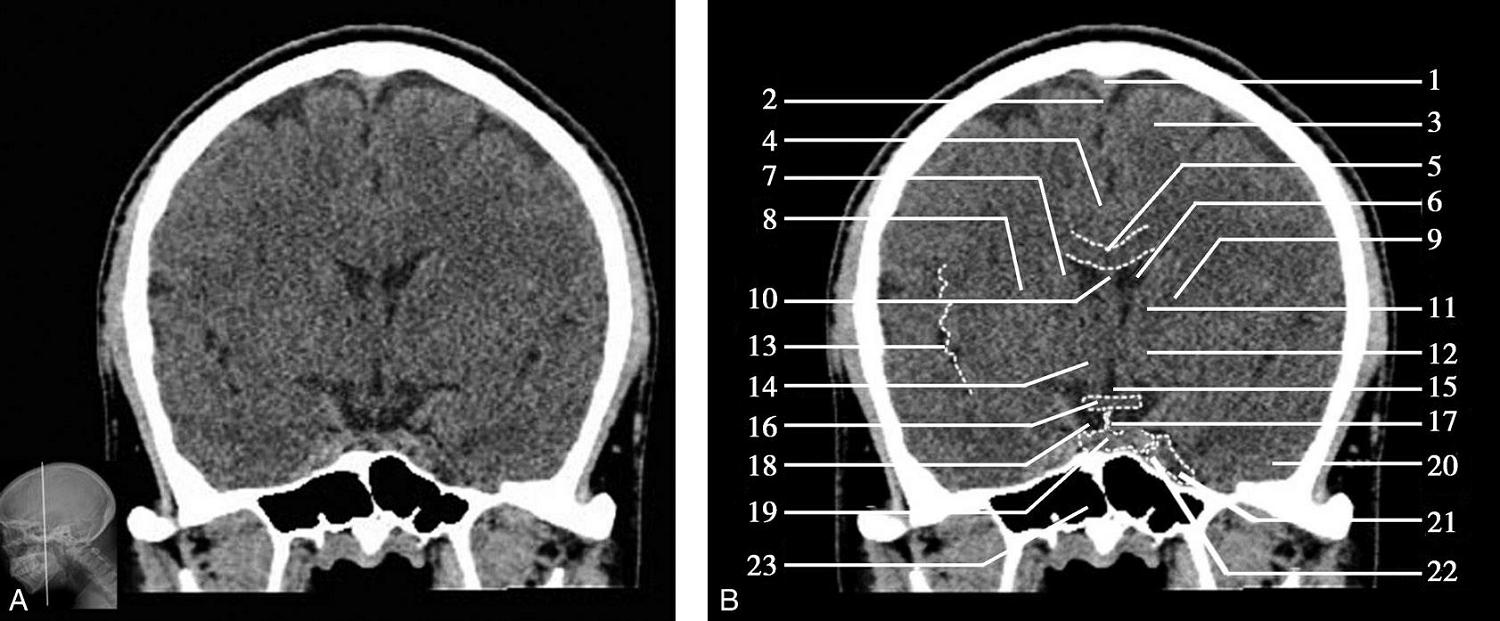

重要结构:视交叉、尾状核头、额叶、颞叶、外侧裂池(图1-2-52、图1-2-53)。

图1-2-52 视交叉层面

A.冠状面;B.冠状面标注

1.上矢状窦;2.大脑镰;3.额叶;4.扣带回;5.胼胝体体部;6.侧脑室前角;7.尾状核头部;8.内囊前肢;9.透明隔;10.豆状核;11.隔核;12.伏隔核;13.视交叉;14.鞍上池;15.外侧裂池;16.前床突;17.颞叶;18.海绵窦;19.蝶窦

此层面正中线上部有大脑纵裂池及其内的大脑镰,大脑镰的上端与上矢状窦相连,下端毗邻胼胝体体部,胼胝体纤维连接双侧额叶。双侧额叶的外侧面,自上而下有额上回、额中回及额下回。胼胝体体部上方大脑镰的两侧有扣带回及扣带沟。胼胝体体部下方正中是透明隔,其两侧近似三角形为侧脑室前角,侧脑室前角顶壁为胼胝体,内侧壁上部为透明隔,底壁由隔核与伏隔核组成,外侧壁为尾状核头部。尾状核头外侧依次为内囊前肢、豆状核、外囊及屏状核。内囊位于尾状核头的外下方,是大脑皮质与皮质下中枢间的上下行纤维组成的投射纤维的主要通路。豆状核位于内囊的外下方,分为内侧的苍白球及外侧的壳核。胼胝体嘴部下方自上而下依次为大脑纵裂池、视交叉、鞍上池。视交叉两侧外下方为前床突的骨性断面,前床突内下方为海绵窦,其内可见颈内动脉断面,前床突外侧为两侧颞叶,两侧额叶与颞叶借外侧裂池分隔,额叶位于外侧裂池上方,颞叶位于外侧裂池下方。海绵窦下方中线区为蝶窦,蝶窦下方中部为鼻腔,鼻腔两侧为颞下窝。